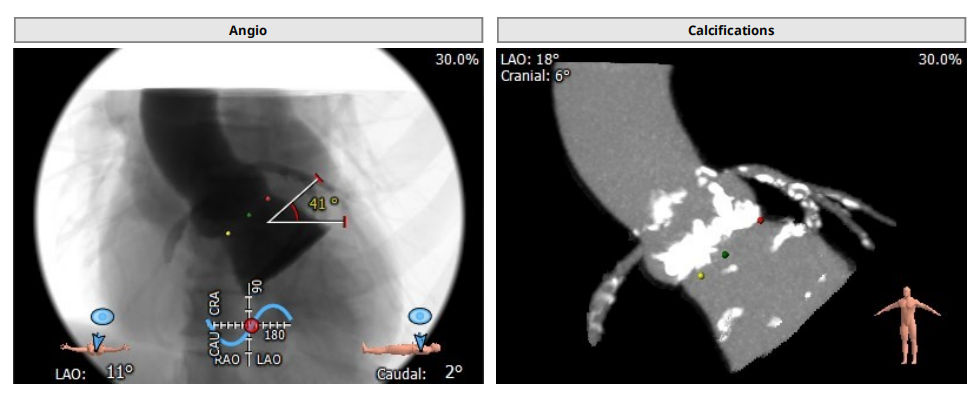

结合患者术前影像学检查结果,考虑到患者的入路血管病变及主动脉瓣钙化情况,拟选用稍小尺寸26mm的SAPIEN 3瓣膜,手术操作难点在于外周血管迂曲带来的并发症风险,以及瓣膜极重度钙化导致的跨瓣和释放困难。

23mm球囊扩张效果良好,造影显示几乎无瓣周漏,故使用输送系统装载26mm的瓣膜,借助双重调弯功能顺利通过主动脉弓并跨过自体瓣膜,精确定位释放位置之后,在180bpm快速起搏下展开释放瓣膜。可见患者瓣膜钙化严重,输送系统难以跨瓣,注意释放过程尽量缓慢。

经造影及超声检查确定无中心返流,仅轻度瓣周返流,瓣膜植入成功。